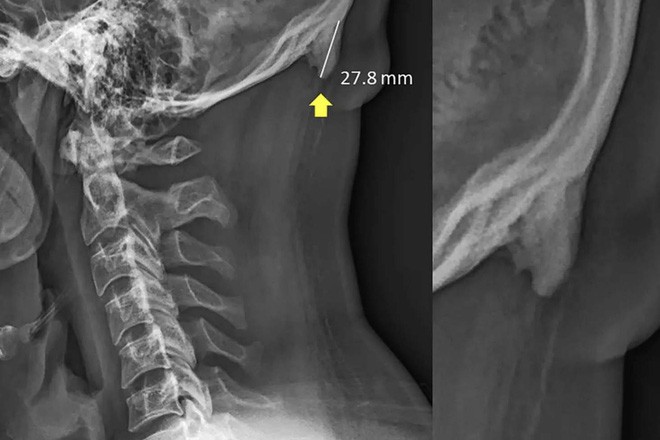

Mới đây, các chuyên gia từ ĐH Sunshine Coast (Úc) đã thực hiện một nghiên cứu trên 1.200 người trẻ trong khoảng từ 18 - 30 tuổi. Họ đã theo dõi bản chụp X-quang hộp sọ của các ứng viên, và phát hiện ra một hiện tượng hết sức bất ngờ: Khoảng 1/3 trong số đó có một gai xương xương mọc ra từ phía sau hộp sọ, trông giống như một chiếc sừng nhỏ vậy.

Nguyên nhân được cho là vì thói quen nghiêng đầu về phía trước khi sử dụng smartphone và các thiết bị điện tử cầm tay khác. Hành động này khiến trọng lượng dồn từ đốt sống cổ về phía các cơ sau đầu, khiến hộp sọ phải mọc thêm đốt xương để giảm bớt áp lực.

Có thể so sánh điều này với hiện tượng da mọc thành chai tay khi liên tục phải chịu áp lực cọ xát từ môi trường bên ngoài.

Thông thường, đốt xương này chỉ ẩn bên trong đầu, nhưng có một số trường hợp cảm nhận được họ có nó. Và dù chưa ghi nhận trường hợp nào lộ hẳn ra ngoài, nhưng hiện tượng này cũng cho thấy một sự thực là con người ngày nay đang sử dụng điện thoại quá nhiều.